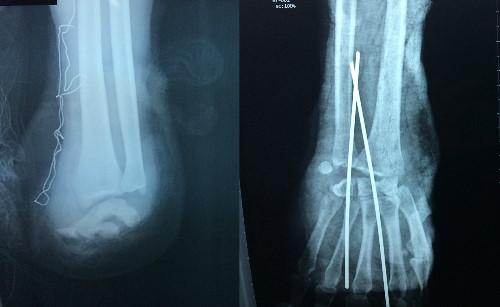

Hình chụp X-quang cho thấy tay trái bệnh nhân bị đứt lìa, tay phải đứt cơ. Ảnh: Hòa Khánh.